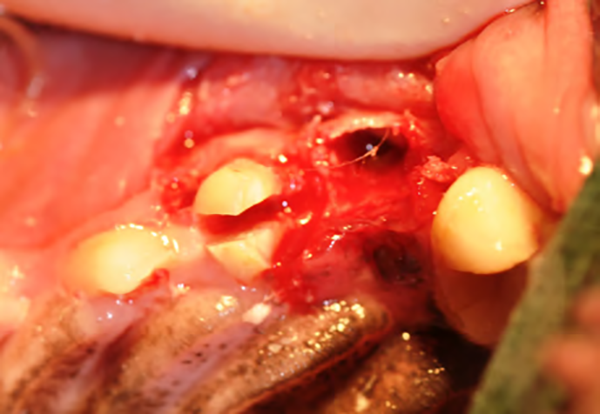

Figure 2E : Une fois la racine mobilisable, elle est saisie à l’aide d’un davier et mobilisée par mouvements lents et continus de traction et rotation jusqu’à son extraction en douceur.

Figure 2F : Les deux racines distales sont séparées (fraise fissure sous irrigation) avant d’être mobilisées et extraites de la même façon que pour la racine distale.

Figure 2G : Une fois la dent extraite, les alvéoles sont curetées, les crêtes alvéolaires sont « lissées » à la fraise boule sous irrigation (alvéoloplastie) et le lambeau est suturé à la muqueuse palatine par des points séparés (fil monofilament résorbable).